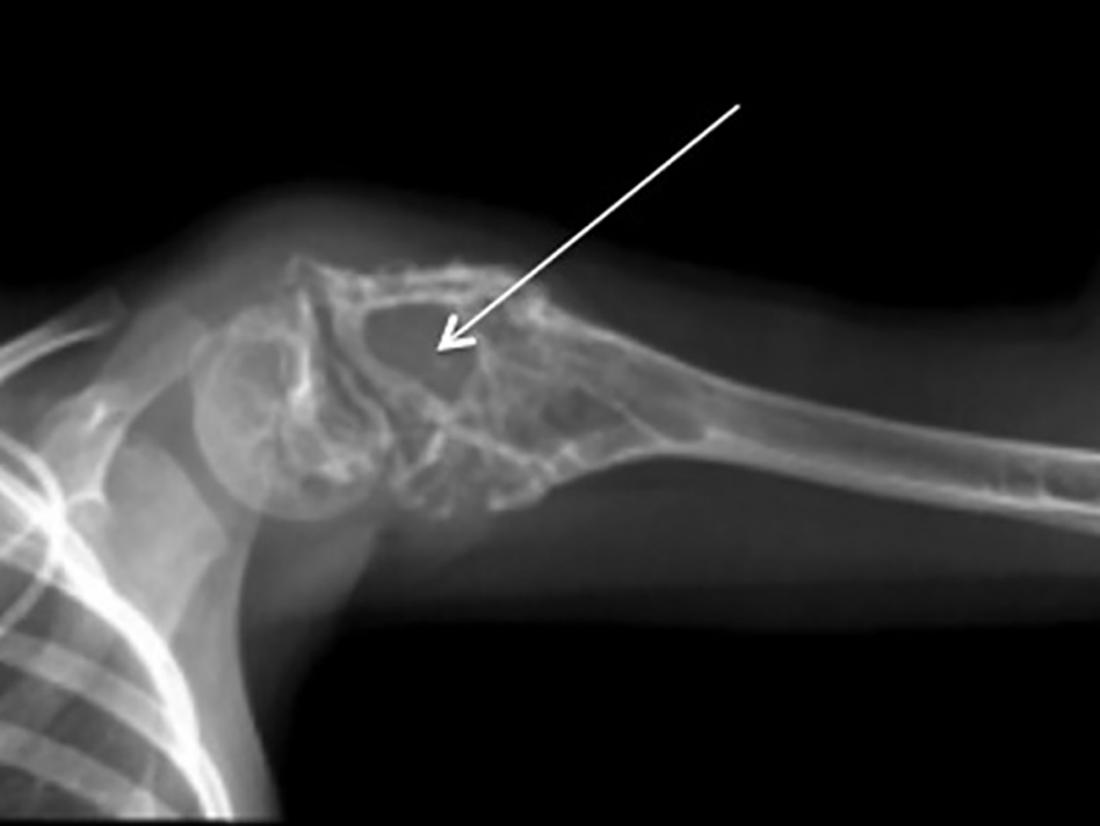

Sarcomul lui Ewing este o formă rară de cancer osos, care apare mai frecvent între vârstele de 10-15 ani.